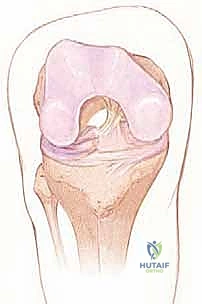

يقع الرباط الصليبي الأمامي في قلب مفصل الركبة، ويمتد بشكل مائل من الشق بين اللقمتين (Intercondylar notch) في عظم الفخذ، نزولاً إلى السطح العلوي لعظم الظنبوب (القصبة).

من الناحية الوظيفية والتشريحية، لا يعمل الرباط كوحدة واحدة، بل ينقسم إلى حزمتين رئيسيتين تعملان بتناغم عجيب:

1. الحزمة الأمامية الإنسية (Anteromedial Bundle - AM): هذه الحزمة تكون مشدودة بشكل رئيسي عندما تكون الركبة في وضعية الانثناء (Flexion). وظيفتها الأساسية هي منع عظم القصبة من الانزلاق للأمام بعيداً عن عظم الفخذ.

2. الحزمة الخلفية الوحشية (Posterolateral Bundle - PL): تكون هذه الحزمة مشدودة عندما تكون الركبة في وضعية الاستقامة الكاملة (Extension). هذه الحزمة هي المسؤولة الأولى عن توفير الثبات الدوراني للركبة، وهي التي تمنع الركبة من الالتواء أثناء تغيير الاتجاه المفاجئ.